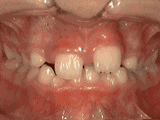

phase i

Patient's parents were concerned about both aesthetics and the health of the erupting permanent teeth when they brought him to the orthodontist at age eight. The lower front teeth were crowded and they touched the palate, and the upper front teeth were extremely displaced from their normal positions. After twenty months of Phase I treatment with an expander and partial braces, patient's appearance and dental function was vastly improved.